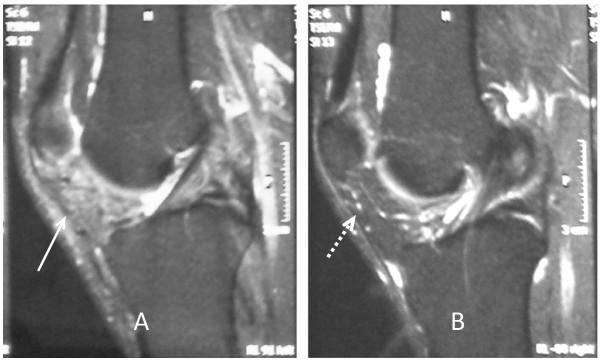

We report the case of a large infrapatellar fat pad ganglion in a 37-year-old Greek man with chronic knee discomfort. The ganglionic cyst originated from the infrapatellar fat pad and had no intrasynovial extension. The final diagnosis was determined with magnetic resonance imaging of the knee, and the lesion was treated with surgery.

我们报告一例37岁希腊男性患有髌下脂肪垫大型神经节囊肿且伴有慢性膝关节不适的病例。神经节囊肿起源于髌下脂肪垫,无滑膜内延伸。通过膝关节磁共振成像确定最终诊断,并对病变进行手术治疗。